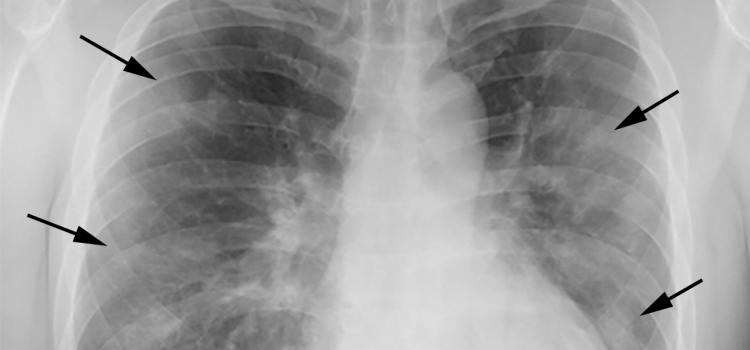

The psoas muscle edge is clearly defined on the left but not on the right. Example of the silhouette sign on chest X-ray. There is no evidence of bowel obstruction or perforation.

X-rays penetrate different objects more or less according to their density. For example a radiologist may describe the border of the heart as being silhouetted or obscured by an adjacent lung process. V x-ray take an x-ray of something or somebody The doctor x-rayed my chest v x-ray examine by taking x-rays.